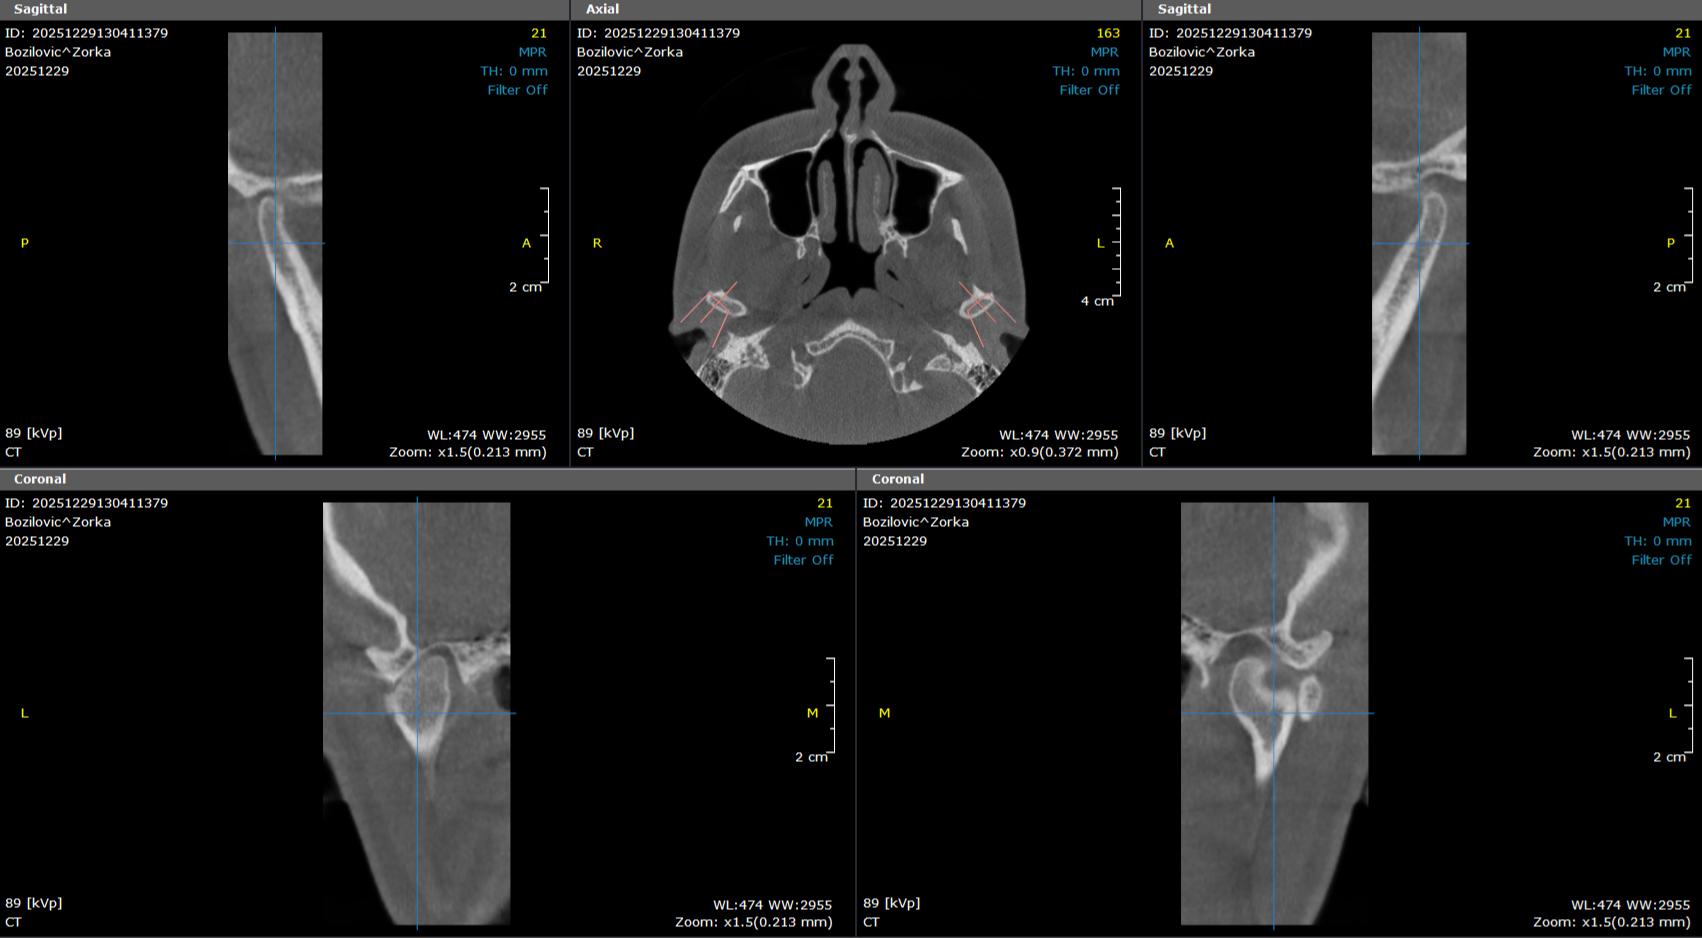

tempomandibularni zglob

Snimak tempomandibularnog zgloba – TMJ, u 3d i 2d modu, omogućava detaljan uvid u položaj i funkciju viličnog zgloba. Koristi se u dijagnostici bolova u vilici, škljocanju pri otvaranju usta, poremećaju zagrižaja i drugih problema vezanih za funkciju viličnog zgloba.

6 000,00 rsd